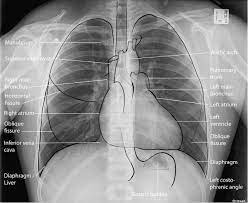

L these two lobes are separated by a major fissure, identical to that seen on the right side, although often slightly more. Dr andrew dixon ◉ and dr jeremy jones ◉ et al. Recognizing normal anatomy on the cxr is key to understanding and interpreting abnormalities. There are many approaches to cxr interpretation, each trying to ensure that key abnormalities are identified and no area is. Vq mismatch and hyponatremia lectures have been popular. Few providers (including mds) are comfortable interpreting their own films. © 2005 adam guttentag, md. Standard frontal chest radiograph (roentgenogram) — upright;

Interpretation of the chest x ray. Chest x ray is probably the most common imaging test. In addition to text and pictures, this tutorial contains interactive features which supplement the text and make it a more dynamic learning. Examination of the chest x ray is a process which requires a systematic approach. Standard frontal chest radiograph (roentgenogram) — upright; Recognizing normal anatomy on the cxr is key to understanding and interpreting abnormalities. Few providers (including mds) are comfortable interpreting their own films. In fact every radiologst should be an expert in chest film reading. Normal heart size is half of the chest width. Generally speaking, a normal cxr should have the lungs looking like zebras in that they are all black with strips. The aim of this study was to investigate the diagnostic accuracy of cxr interpretation by reporting radiographers (technologists). The chest radiograph remains the most important method of chest imaging, providing an easily accessible, inexpensive, quick, and effective diagnostic tool. Learn about chest x ray interpretation with free interactive flashcards.

Normal heart size is half of the chest width. Standard frontal chest radiograph (roentgenogram) — upright; In fact every radiologst should be an expert in chest film reading. Generally speaking, a normal cxr should have the lungs looking like zebras in that they are all black with strips. These images were saved with anonymous biodata for iom radiology collection and teaching purposes.